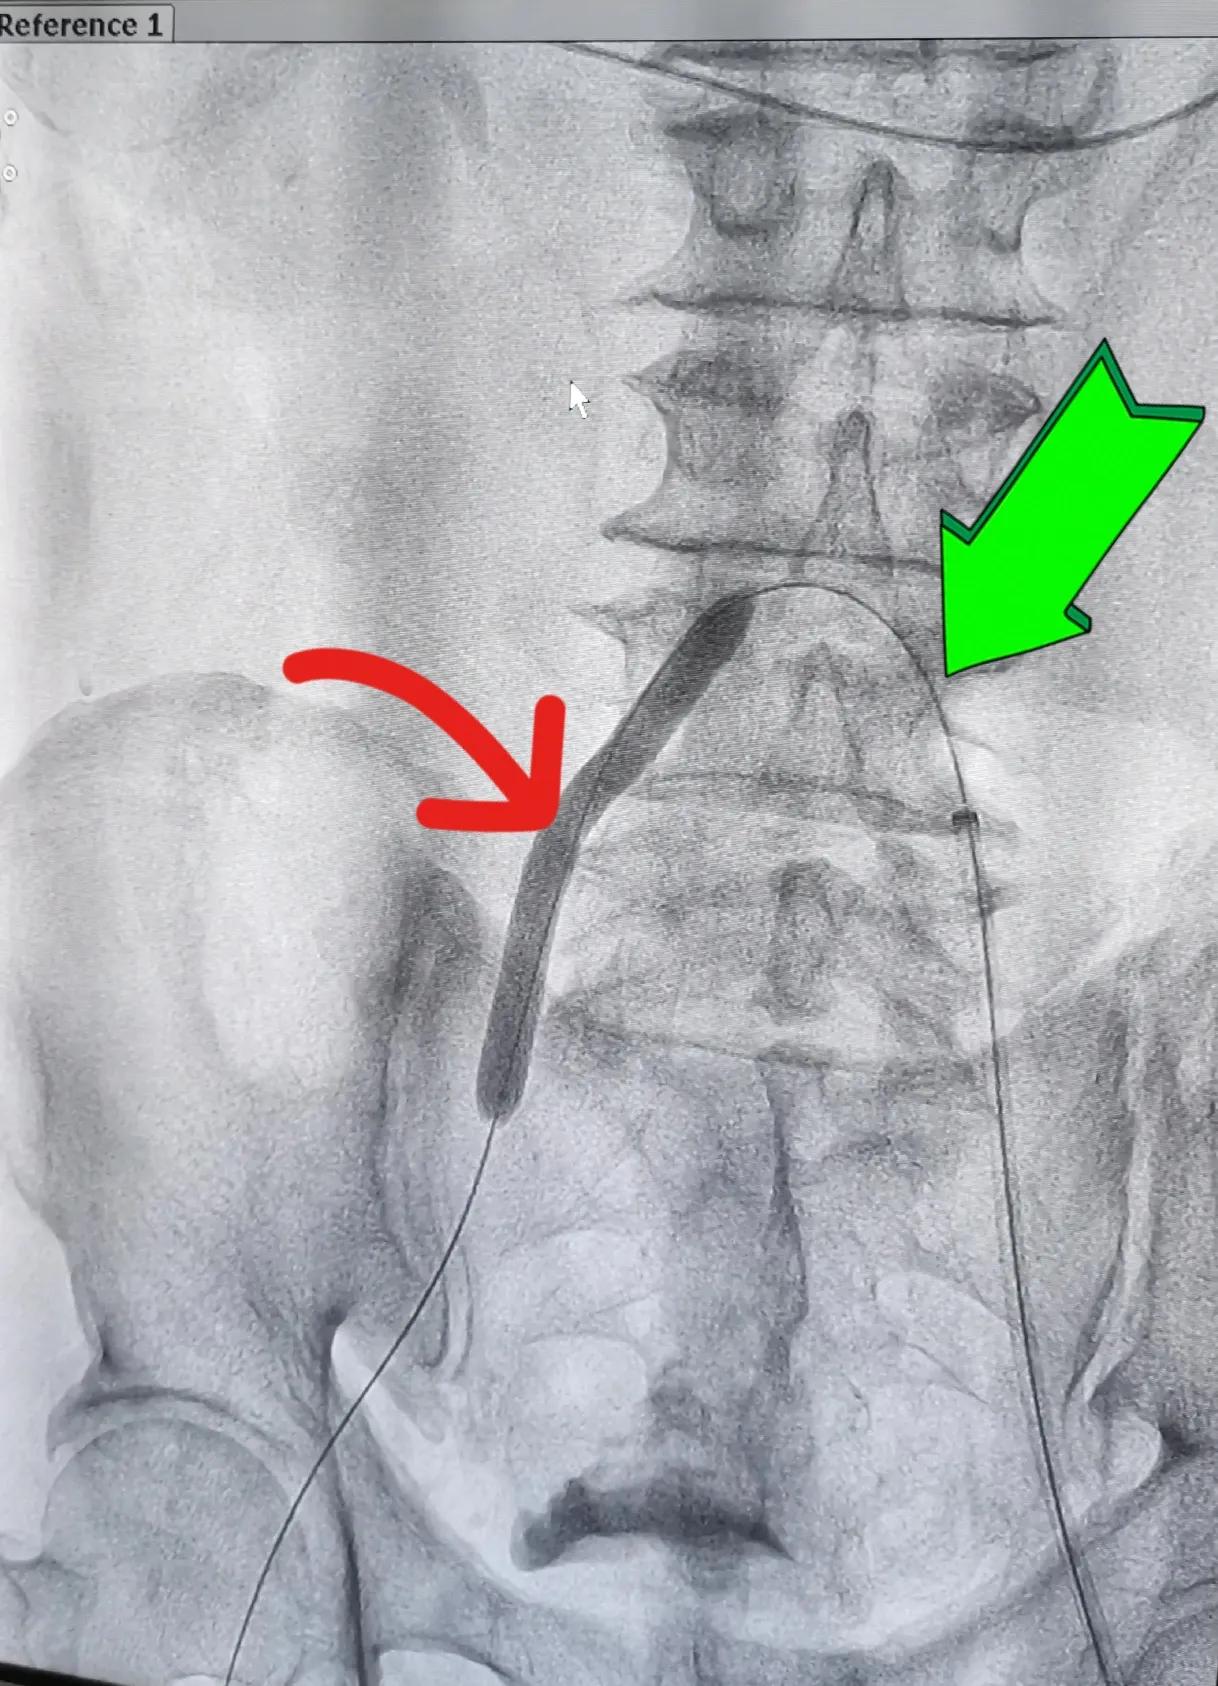

图二:红色箭头所指在股动脉最狭窄处用球囊扩张后植入支架使股动脉管腔变大,绿色箭头所指是泥鳅导丝

图一至图五是2022年9月初浙江普陀医院(公立)骨科医生对退休教师李某某髂动脉,股动脉闭塞性动脉硬化进行介入治疗前后血管造影对比。显示血管内支架植入后血管形态非常好,患者出院后术后一个月观察,走路时下肢疼痛完全消失,间歇性跛行症状消失,两下肢功能完全恢复。